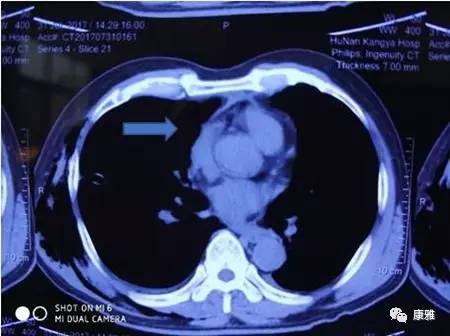

图2术后胸部CT(箭头所指处肿瘤消失)